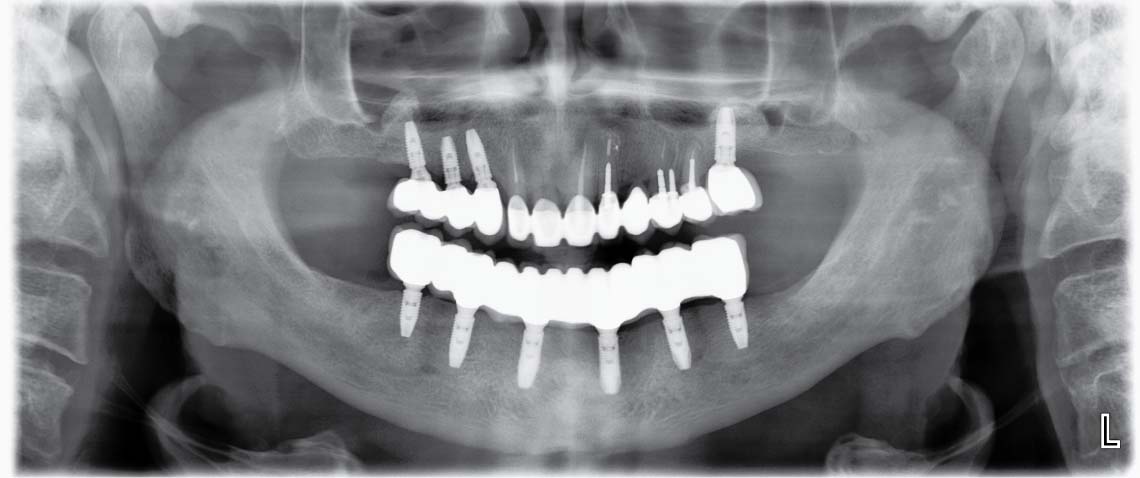

Случай 1: Лечение с импланти